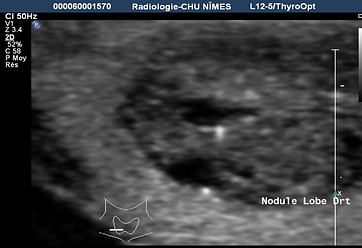

Cáncer papilar UE TIRADS 5

Microcalcificaciones

Rotura de cápsula